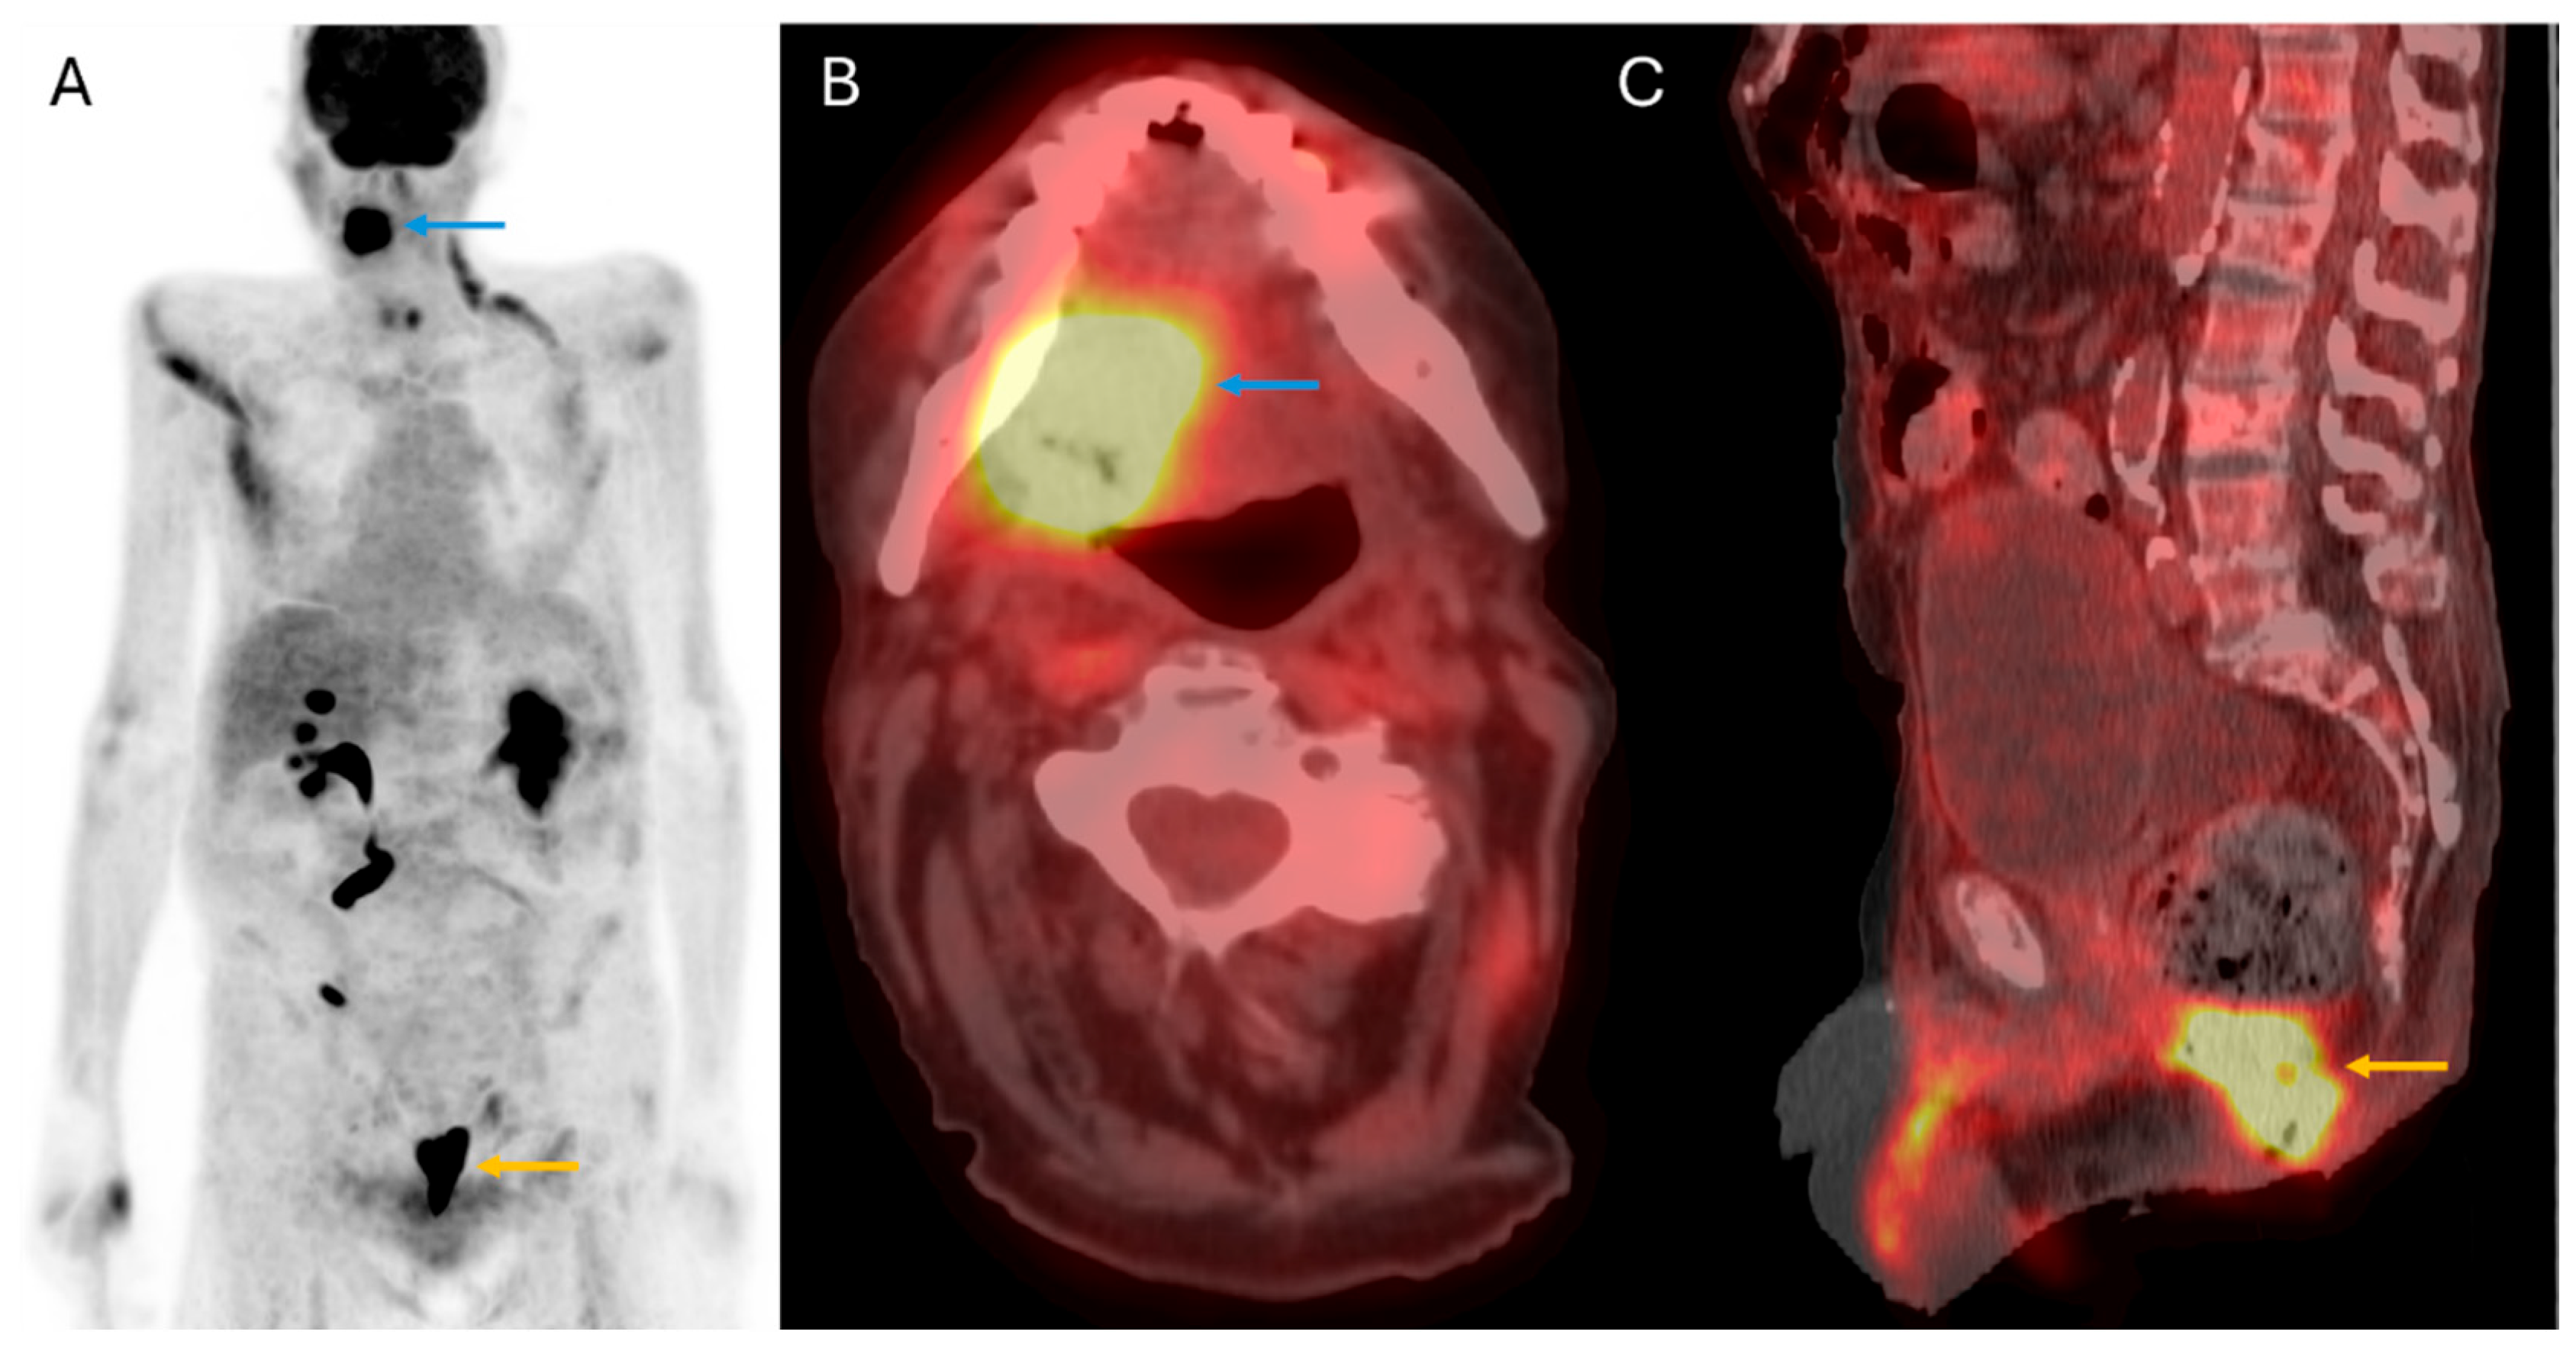

3. Primary Tumor Staging

6. Occult Primary and Synchronous Primary Malignancy Detection